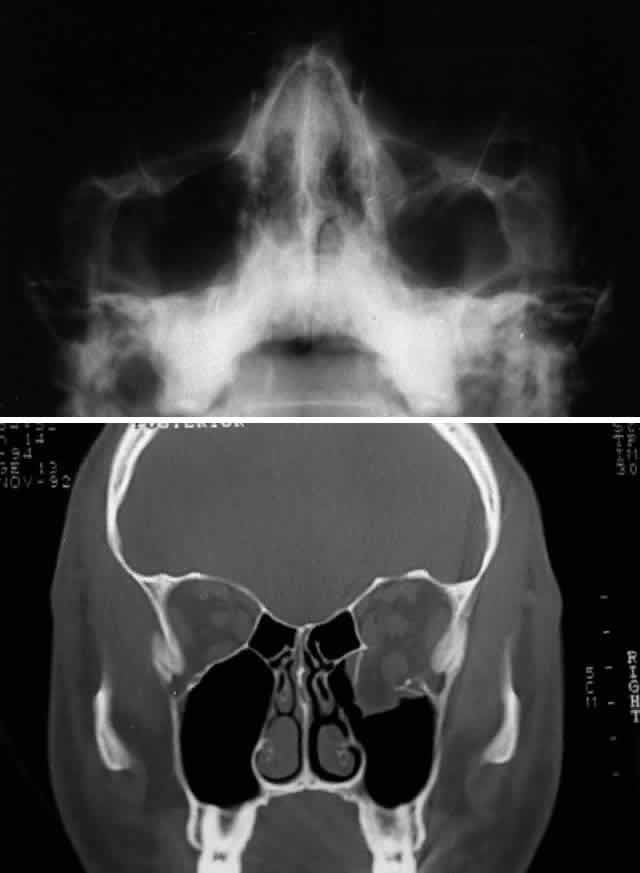

After the history and physical examination, consideration is given to further assessment of the orbital injury with radiologic imaging. The indications for radiologic imaging area are based on the physician's assessment of the injury and include gross orbital and facial deformity, limitation of ocular motility, and associated neurologic injuries. CT is the imaging modality of choice in the assessment of orbital/craniofacial fractures because it provides excellent detail of the bony injury as well as the orbital soft tissues in most cases (Fig. 4). Ideally, both axial and direct coronal views are preferred. Coronal views are necessary for adequate imaging of the orbital floor and orbital roof. With direct views, 3-mm views (cuts) are usually adequate. In cases in which the patients cannot be positioned for direct coronal imaging, coronal reconstructions can be performed, provided that finer (1.5-mm) axial cuts are used. Reconstructed coronal images lack the resolution of direct coronal images, but they are usually adequate when direct coronal imaging cannot be obtained. Spiral CT, which allows rapid imaging and multiplanar formatting, will likely become useful in the assessment of orbital trauma as this newer technology becomes increasingly available.

Fig. 4. Same patient as depicted in Figure 3. A. Water's view. Facial x-ray shows ill-defined left inferior orbital floor fracture with soft tissue mass in superior left maxillary sinus. B. Coronal CT scan shows superior resolution of left orbital floor defect, with prolapse of orbital soft tissues into the maxillary sinus. Note distortion of left inferior rectus muscle. Floor defects greater than 50% are more likely to produce enophthalmos.

Craniofacial fractures can also be imaged with the use of three-dimensional (or, more accurately, pseudo-three-dimensional) reconstructions. Although three-dimensional reconstructions can provide a perspective that may help conceptualize the extent of the injury, they are not essential for treatment. Three-dimensional imaging has some disadvantages: besides entailing additional cost, time, and radiation, it obscures the intricate details of fracture anatomy in the middle orbit by summing individual images. This technique also provides no information regarding the relationship between bone and soft tissues, which is particularly important in the assessment of orbital injuries. Standard two-dimensional CT scans, however, adequately show the degree of orbital bony disruption as well as the associated orbital soft tissue changes, particularly the relationship of the extraocular muscles (and orbital connective tissues) with the fracture site.1

Before CT scanning was readily available, facial x-ray series were used in the radiologic assessment of orbital fractures. Typical views included Caldwell's (anteroposterior) view, Waters' view, lateral view, and submental vertex view (particularly good for viewing the zygomatic arches). Waters' view, which is obtained with the chin slightly elevated, is considered the most useful x-ray view for imaging the orbital floor, inferior rim, and maxillary sinus. Because CT scans are superior to x-rays in terms of sensitivity and reliability, in most situations today plain orbital/facial x-rays are obtained only when a CT scan is unavailable or when only very minimal injury is suspected. Magnetic resonance imaging (MRI), although able to image orbital soft tissue exquisitely well with a small surface coil, is generally of limited usefulness in the initial assessment of orbital/craniofacial injuries because of its limited ability to image bone. It is contraindicated in cases of suspected retained ferromagnetic foreign bodies. MRI may have a secondary role in the management of orbital trauma in cases where CT scanning suggests the presence of soft tissue injury, such as intramuscular hemorrhage or sub-dural optic nerve sheath hemorrhage. In such cases, the better soft tissue resolution potentially available with MRI may allow more specific diagnostic interpretation.2